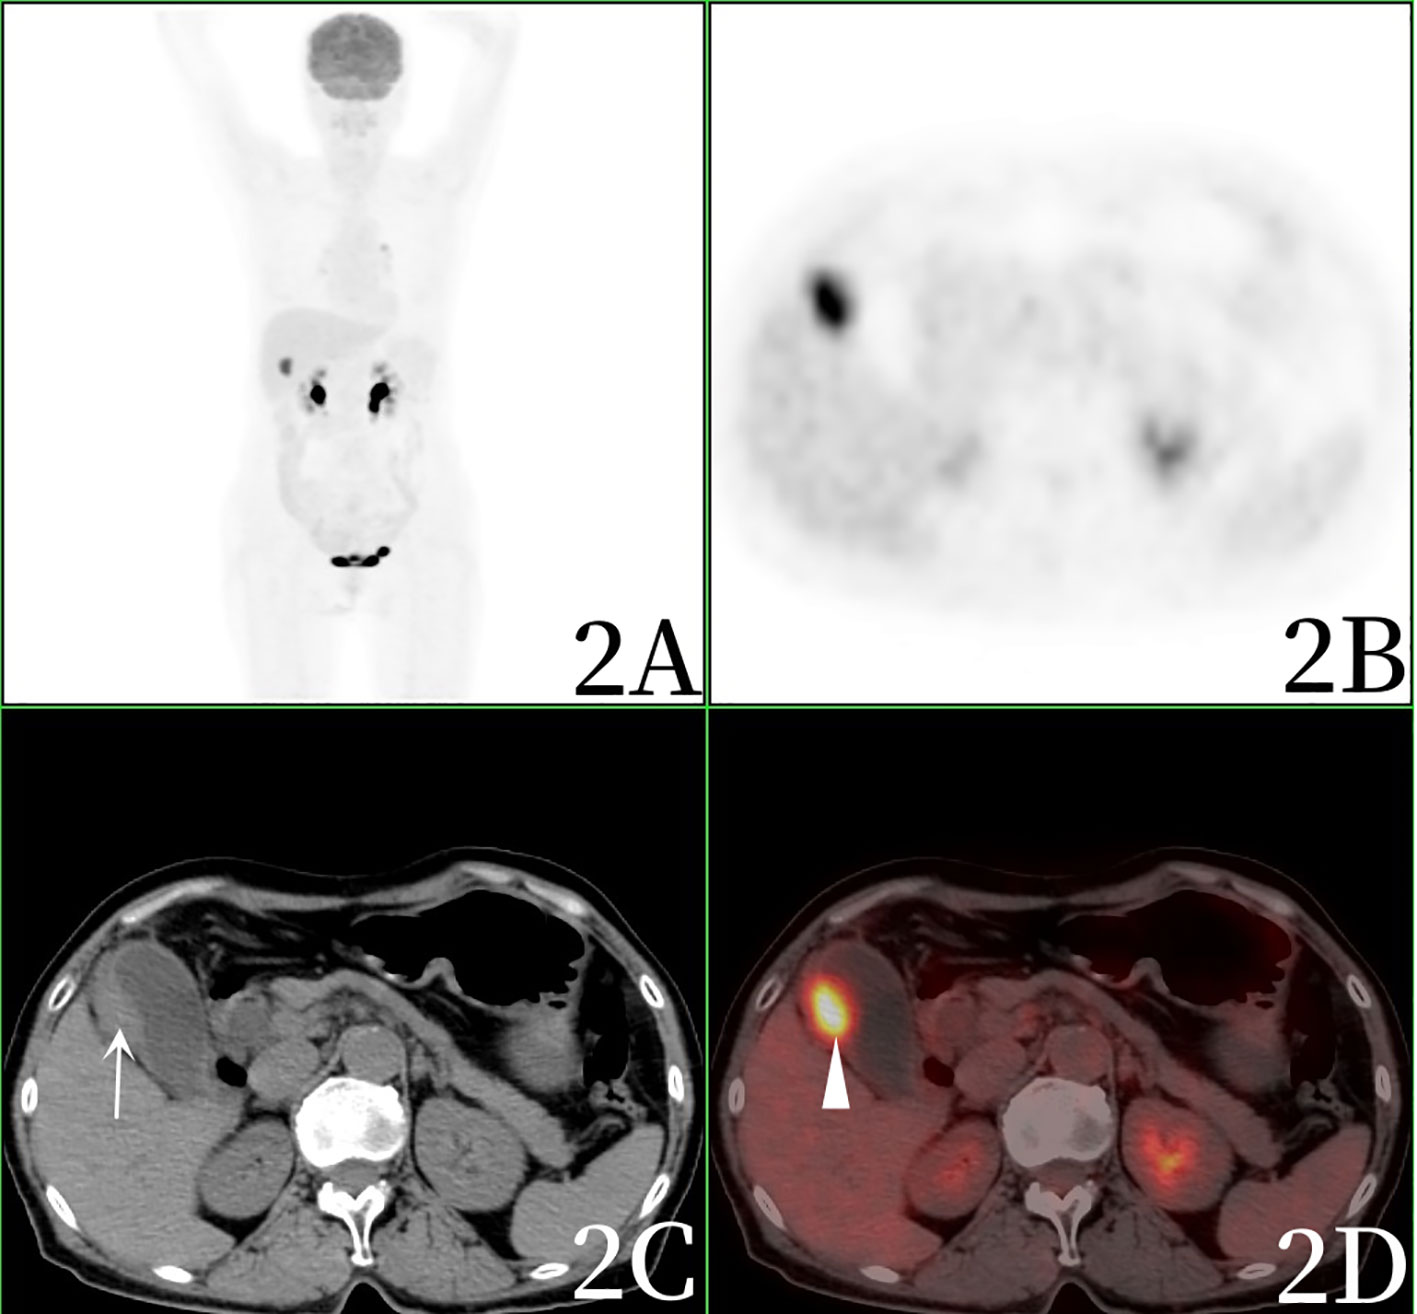

In Newly Diagnosed Diffuse Large B Cell Lymphoma Determination Of Bone

Comparison Of 18F FDG PET And Bone Scintigraphy In Detection Of Bone

18F FDG PET And 18F FDG PET CT For Assessing Response To Therapy In